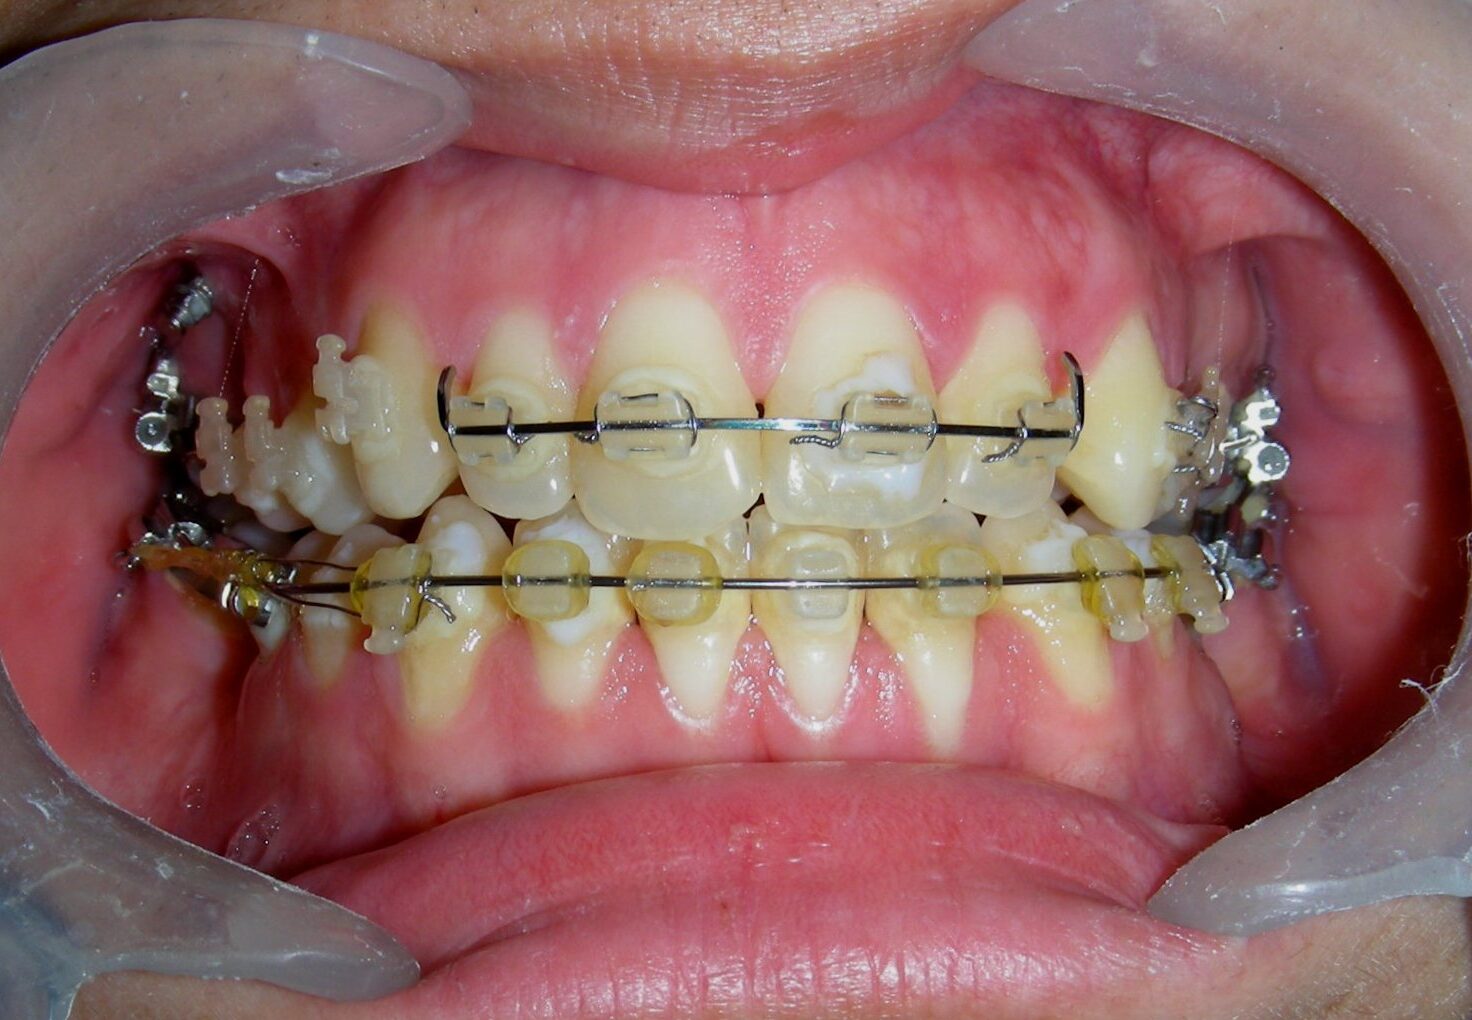

The upper brackets were bonded solely for the purpose of providing stability to the utility arch . Following the hierarchically structured treatment plan, we proceed with the alignment and leveling phase in order to enable mesialization of the posterior segments using sliding mechanics, which works effectively in conjunction with Roth prescription brackets .022.

A progressive archwire sequence was used for alignment, leveling, and three-dimensional control.

- .018″ × .018″ Blue Elgiloy sectional archwire was placed in three segments in the maxillary arch to maximize the effectiveness of Class II intermaxillary elastics, in conjunction with space closure (mesialization) in the mandibular arch.

- 017″ × .025″ Blue Elgiloy sectional leveling archwire beetwen # 35-37 and 45-47

- 017″ × .025″ Stainless Steel (SS) + Closed-coil NiTi springs were activated between the molars and anterior segment

- 019″ × .025″ Stainless Steel (SS)

After two years of treatment using appropriate biomechanics, the overbite was successfully corrected from -8 mm to +1 mm, achieving complete closure of the anterior open bite without exacerbating the patient’s lower facial third vertical proportions. At this stage, occlusal contacts were verified using articulating paper, and functional movements of the canines and incisors were evaluated to ensure proper anterior guidance and disclusion patterns. The patient was then referred to speech therapy (myofunctional evaluation) as part of the pre-debond assessment protocol.